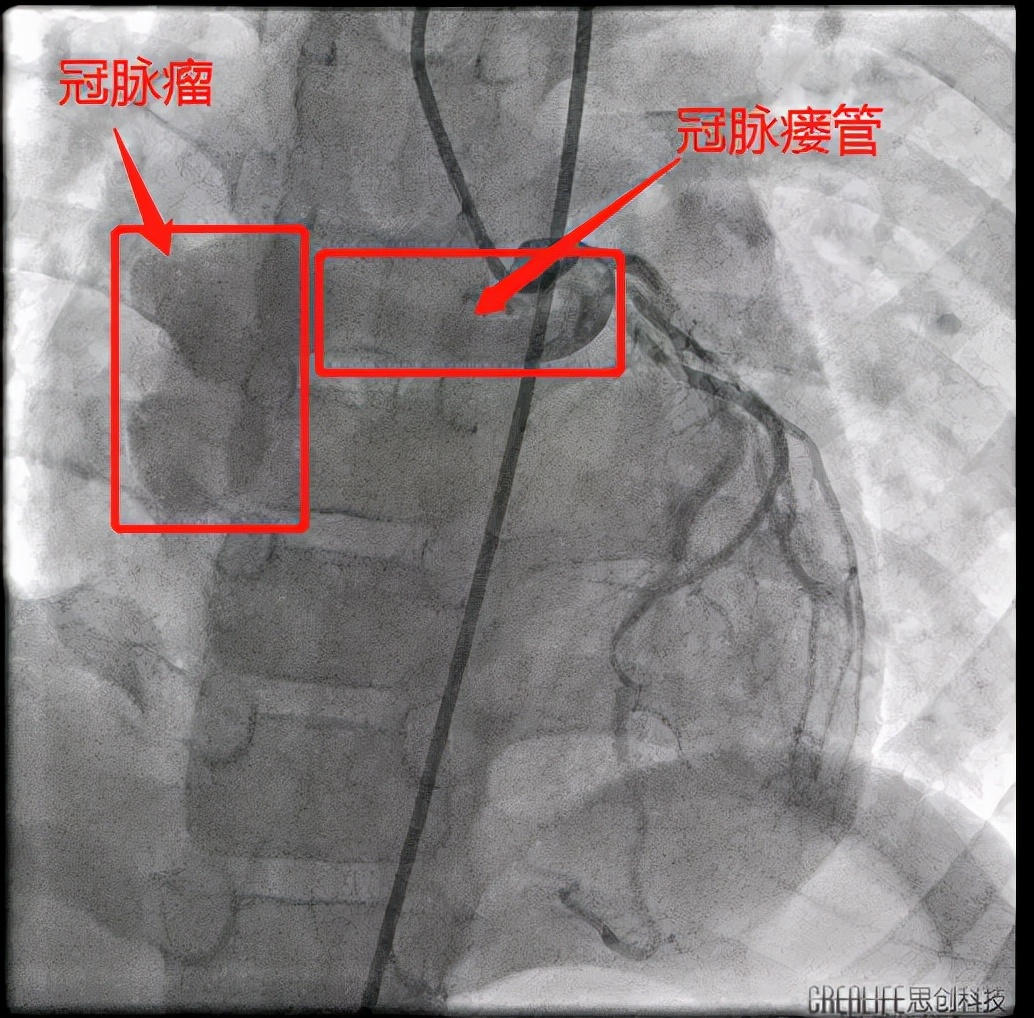

手术在患儿心脏维持正常跳动的情况下进行,术中在X线透视下操作导丝和导管通过左冠状动脉后找到瘤体并充分显影,再把导丝送入瘤体内操作。该患者瘘管有较大的冠状动脉瘤,瘤体的破口小,须把导丝穿过瘤体破口后,由股静脉送出才能建立动静脉轨道,再用封堵器进行封堵,手术难度增大。